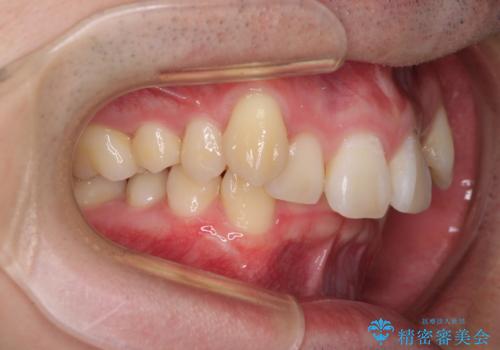

- 八重歯を気にして来院された患者様です。

顕著な上顎の八重歯とディープバイトであったため、上顎の左右第一小臼歯を抜歯することとしました。

犬歯歯根の位置や奥歯の咬み合わせから、ワイヤー装置での治療を強くおすすめいたしましたが、ご本人の強い希望により、妥協的な仕上がりとなることを了解いただき、インビザラインにて矯正治療を行うこととしました。

インビザライン単体で、左右ともに移動の難しい位置に歯根のある犬歯を整えるのは困難と判断し、補助装置を併用することとしました。

ディープバイトや奥歯の咬み合わせなど、インビザライン矯正では限界がありワイヤー装置での治療に及ばない仕上がりとなりました。

ただし、患者様としては八重歯や、それに伴う唇の閉じにくさが改善されたとのことで、納得いく状態での治療終了となりました。